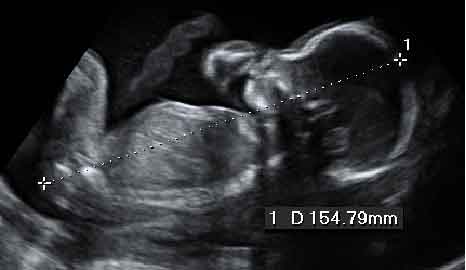

Genitales del sexo masculino

Imágenes de un varón que flexiona las piernas por delante de los genitales, que se pueden distinguir perfectamente.